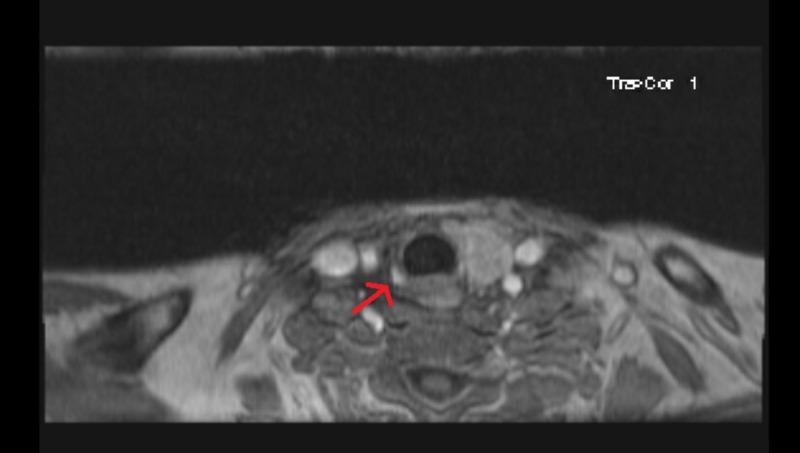

Primary hyperparathyroidism (PHPT) is the third most common endocrine disorder after diabetes and thyroid disease. Most cases of hyperparathyroidism remain clinically silent. The clinical manifestations of hypercalcemia captured in the classic medical student mnemonic of "stones, bones, groans, and psychic moans" are often not found. Sometimes patients can present with unique complications. This case describes perforated peptic ulcer as the first presentation of primary hyperparathyroidism.

原发性甲状旁腺功能亢进症(PHPT)是继糖尿病和甲状腺疾病之后的第三大常见内分泌疾病。大多数甲状旁腺功能亢进症病例在临床上并无明显症状。经典的医学生记忆口诀“结石、骨痛、呻吟、精神错乱”中所描述的高钙血症临床表现往往并不存在。有时患者会出现独特的并发症。本病例描述了以消化性溃疡穿孔作为原发性甲状旁腺功能亢进症的首发表现。